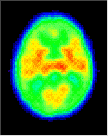

Click on image above to view full-size image.

The high CMRGlc during 3 to 10 years corresponds to the period of exuberant connectivity in humans and is probably required to meet the energy demands of the neuronal processes and synapses that are also in excess by about a factor of two compared to adults. Shown above are PET scans from 3 different ages showing the relative glucose metabolic rate. Beneath the PET scans are drawings showing the relative complexity of the dendritic structure of cortical neurons. The progressive increase in glucose utilization seen in development is consistent with anatomical studies showing an expansion of dendritic fields (and synaptic connectivity) and an increase in capillary density in the human frontal cortex during the same period. Thus, it is possible that the decrease in glucose metabolic rate in the adult reflects a "pruning" of excessive neuronal connectivity and a selective stabilization of the remaining neuronal connections.